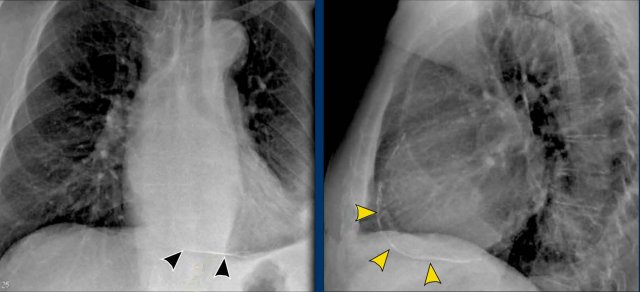

Left Atrial Enlargement

- Patient with a history of chronic mitral valve disease and valve replacement.

- Extreme dilation of the LA leads to bulging of both the right upper cardiac contour (black arrows) and posterior heart border on lateral view (blue arrow).

Right Ventricular Enlargement

First study the PA and lateral chest film and then continue reading.

Findings

- Chest radiographs show massive cardiomegaly, predominantly due to right ventricular dilation (yellow arrow on lateral view).

- Small aortic knob (blue arrow), with dilation of the pulmonary trunk and right lower pulmonary artery.

- Findings suggest a left-to-right shunt with secondary pulmonary hypertension.